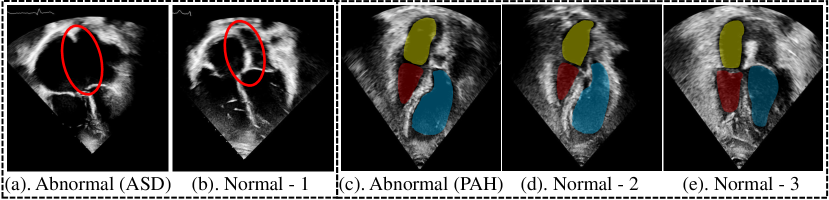

To develop a general approach for cardiac disease assessment, we have identified two important characteristics that encompass a wide range of common cardiac conditions, including EF, Pulmonary Arterial Hypertension (PAH), and Atrial Septal Defect (ASD). Specifically, (1) Local Structure Abnormality refers to cardiac diseases that exhibit clear and distinctive abnormalities in a localized region within a single frame of an echocardiogram video. As depicted in Fig. 1(a-b), a hole (highlighted in Red) can be observed in the atrial septum, enabling the mixing of blood between the left and right atria. (2) Cardiac Motion Abnormality refers to cardiac diseases that may not have clear distinctive abnormalities in a single frame of echocardiogram videos, but can be detected through motion abnormalities of local cardiac structure observed in videos. For instance, in Fig. 1(c-d), there are no clear differences in cardiac structures between PAH patients and normal individuals based on a single frame of echocardiogram videos. Therefore, it is highly necessary to develop an approach to learn a better representation across both temporal and spatial patterns of local cardiac structures via echocardiography.

Figure 1: Five examples from CardiacNet-PAH and CardiacNet-ASD datasets. The appearance between the Atrial Septal Defect (ASD) (a) and normal (b) is easy to distinguish. For (c), (d) and (e), the appearance of cardiac structures in the Pulmonary Arterial Hypertension patient (c) and normal (d) are similar. In contrast, normal cases (d) and (e) show significant differences. Indicates that using a single image is not able to diagnose this type of cardiac disease. Clinically, experienced physicians will use echocardiogram videos with cardiac motion information to make diagnoses.